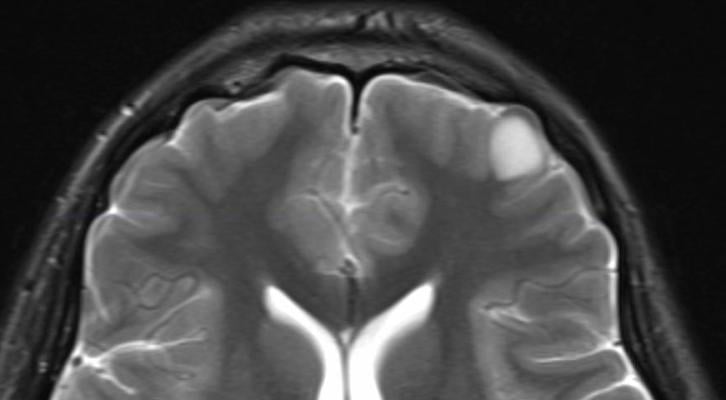

A brain tumor is any tumor in the brain. Which part of my brain is affected by the tumor and what does this region of the brain do? 05/28/2008 05:12am edt gliomas (primary brain tumors) start in the brain or spinal cord tissue. Some tumors, like meningioma, are solid and look like a mass.